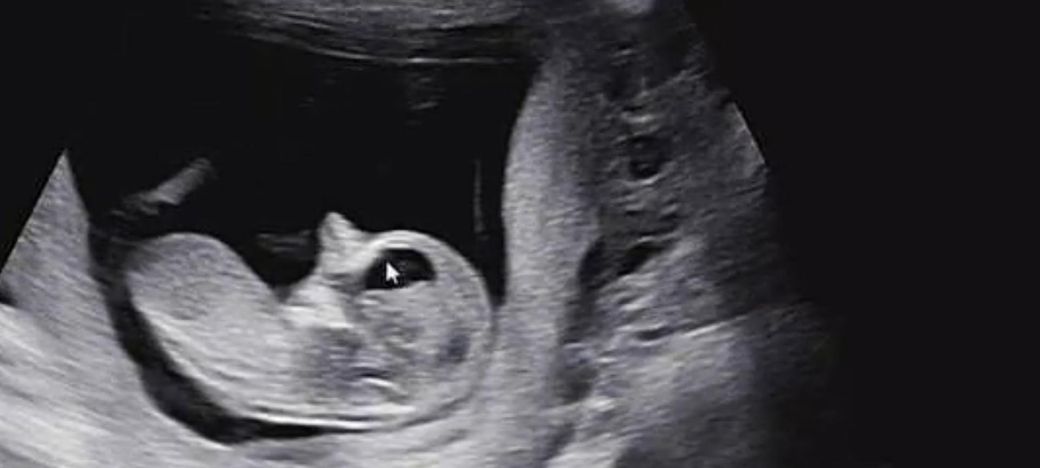

임신 12주차 태아 뇌 초음파 좀 봐주세요ㅜ

임신 12주차 이며 10주차 때 뇌 모양이 신경쓰인다고

앞쪽(이마 쪽)이 신경 쓰인다며 소견서 써줄테니

대학병원 다녀와보라 하시네요ㅜ

12주차 태아의 뇌는 양쪽이 대칭인 나비 모양을 띠는 것이 아주 건강하게 잘 자라고 있다는 신호예요.

초음파상으로 뇌실의 모양이 고르고 깨끗하다면 대부분의 경우 발달이 정상적으로 이루어지고 있다고 보시면 됩니다.

다만 초음파는 각도에 따라 다르게 보일 수 있으니 담당 선생님의 소견을 믿고 마음을 편히 가지시는 게 좋아요.